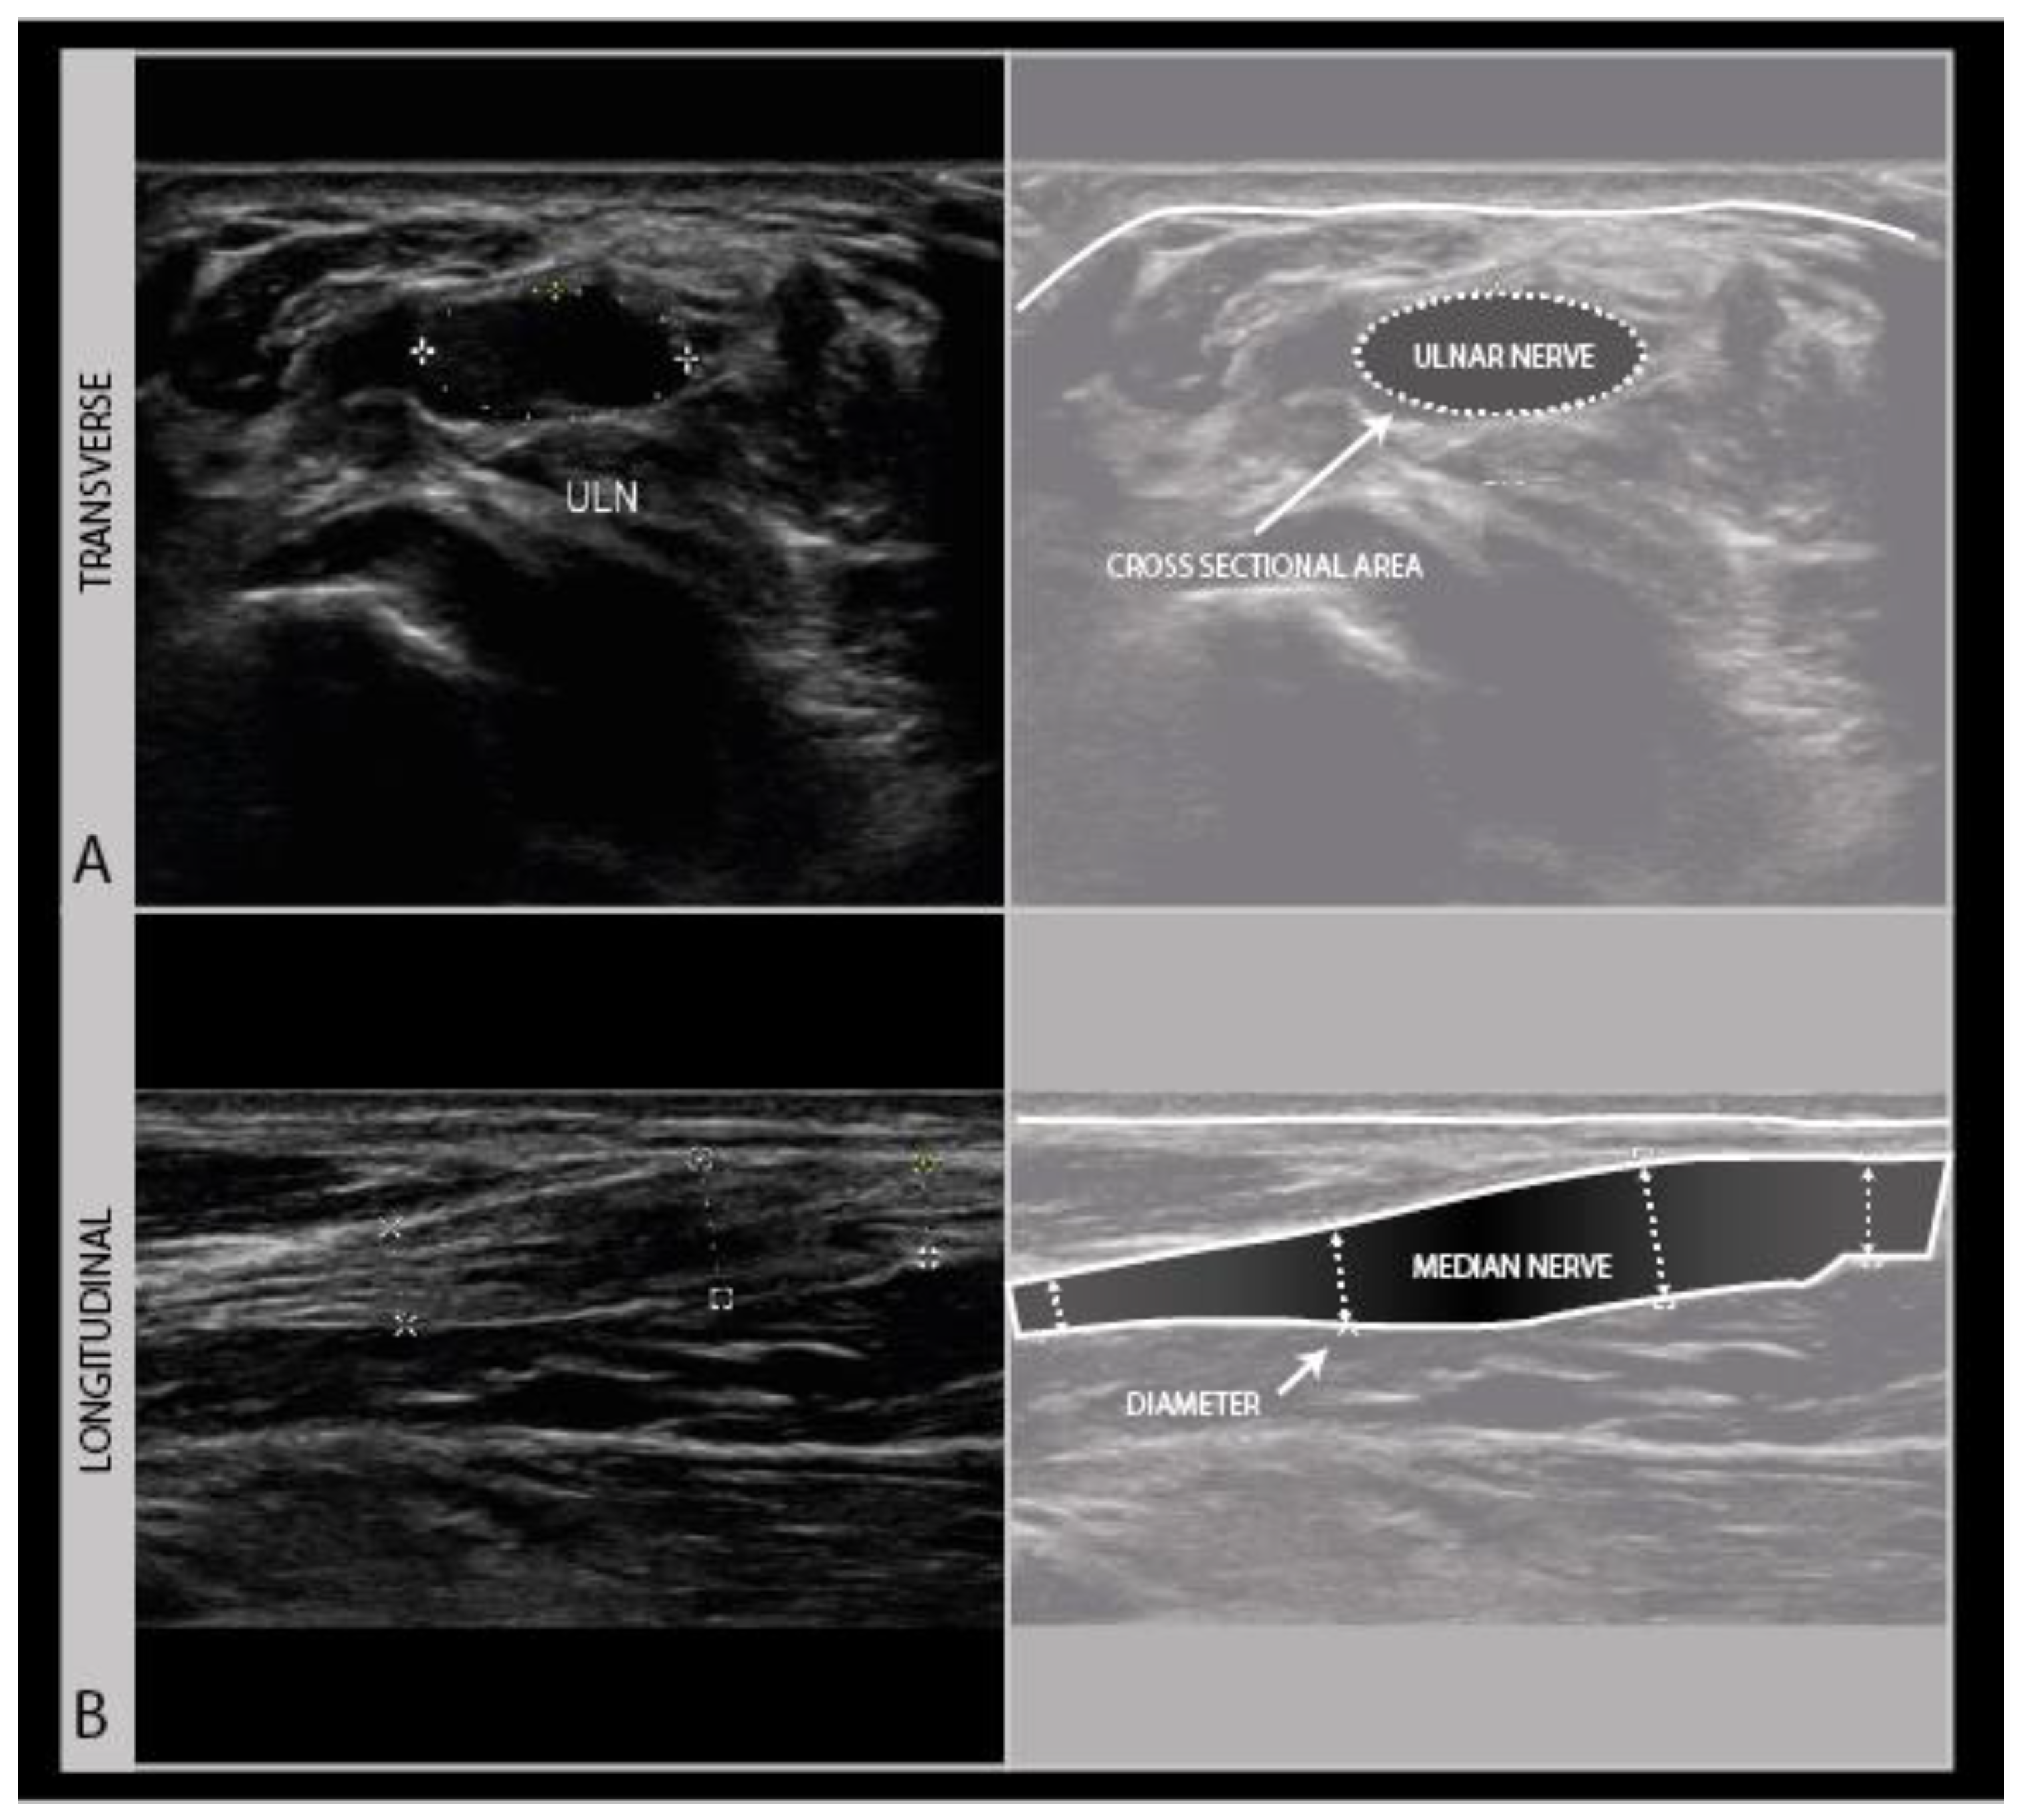

As a standard in neurological nerve ultrasound, transverse imaging is performed for the anatomical identification of the nerve of interest, and to assess its size and architecture for abnormalities. The international agreement is that the nerve size is best measured as a cross-sectional area (CSA) of the nerve traced within the hyperechoic outer epineurial rim [17]. Tracing within the epineurium is the best way to standardize the measurements across patients and over time, as the outer parts of the epineurium blend into surrounding epimysium and fascial structures, which hampers the accurate delineation of the nerve. CSA reference values are available for many nerves [18]. Nerve size increases during growth, so for schoolchildren it is advisable to adhere to a reference that is 50–75% of the adult size depending on age [19].

To assess the nerves for abnormality, it is strongly advised to scan the nerve all the way along its accessible length, looking for sudden changes in size or appearance. When an abnormality is found, it is advisable to also twist the probe 90° around and make a longitudinal image of the lesion site. When measuring neuroma sizes, placing several diameter markers proximal, at and caudal to the lesion site may be helpful (Figure 3).

Figure 3.

Image examples of transverse cross-sectional area (CSA) (A) versus longitudinal diameter measurement (B). A: distal ulnar neuroma; B: distal median nerve neuroma (adult male with a crush injury of the distal forearm). ULN = ulnar nerve.

Longitudinal images are not very good for the identification of the anatomical location, but they are more intuitive for looking at pathology by referring physicians (or patients). It is advisable to annotate images with sparse text to indicate the site, including a nerve name abbreviation such as “MED” for the median nerve, and an indicator for left/right, distal/proximal, etc.). For any nerve that could require surgical intervention, it is recommended to measure the site of abnormality in reference to a recognizable anatomical landmark (e.g., “5 cm distal from the intermalleolar line, 2 cm lateral from the midline” etc.). We strongly recommend making a short ultrasound video scanning from the proximal across a lesion site to a distal one, as ultrasound videos are much easier to interpret afterwards than still images. Finally, the images should be saved to a network location or printed to be saved with the patients’ health records.